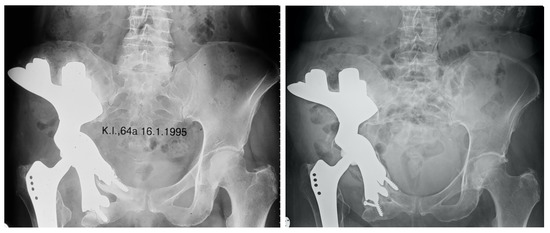

| Femoral stem | ||

| Zweymueller | 12 | 0.7 * |

| Austroprosthesis | 3 | 0.5 * |

| N/A | 5 | 0.9 * |

| Cemented Polyethylene Cup | ||

| Brunswick | 9 | 0.4 * |

| N/A | 9 | 0.9 * |

| Mueller | 2 | 0.3 * |